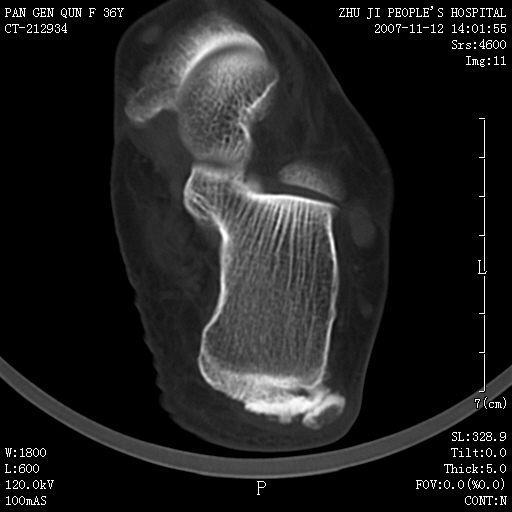

标题: CT10417:F36Y,跟骨跟腱附着处下方骨质密度影,请会诊. [打印本页]

标题: CT10417:F36Y,跟骨跟腱附着处下方骨质密度影,请会诊.

跟骨结节后部肿块半年,无明确外伤史,及红肿热痛.

跟腱附着处骨化致骨化性肌炎。

跟腱附着处骨化致骨化性肌炎